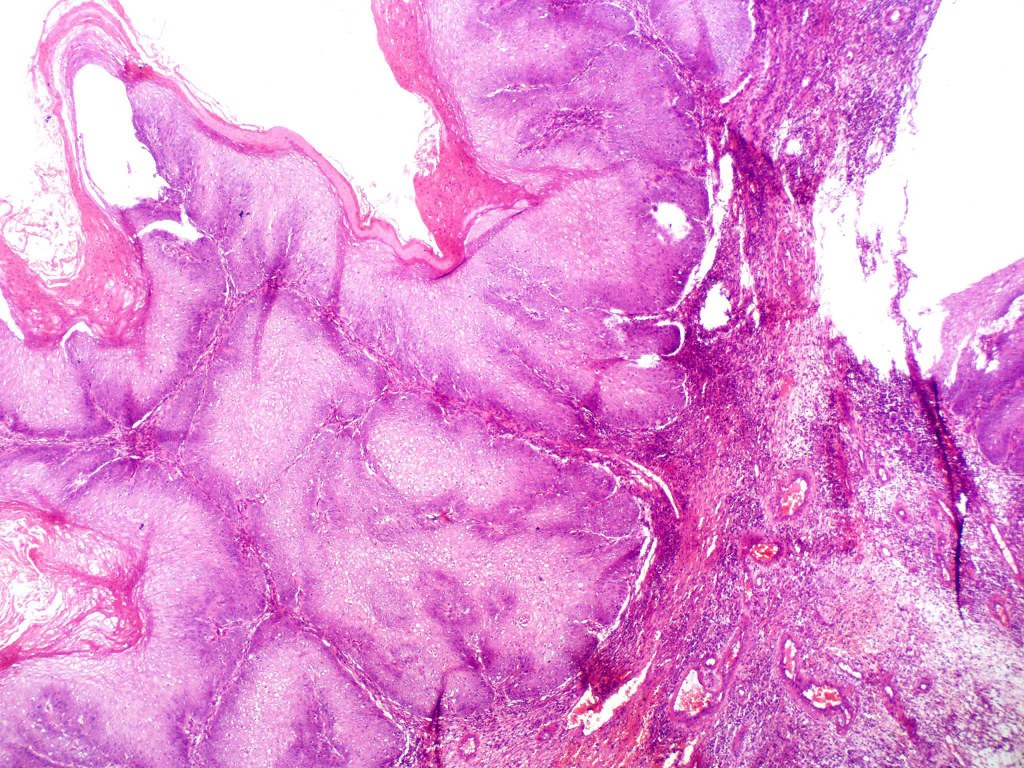

•Often massive hyperkeratosis

•Epidermal verrucous hyperplasia

•Deeply penetrating bulbous processes with a pushing rather than infiltrating lower border

•Well differentiated epithelium characteristically having a ground glass appearance